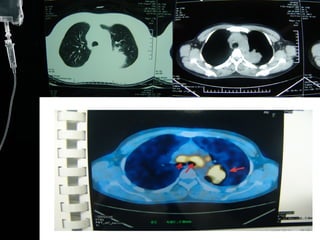

Lung cancer on CT  CT is the most useful in evaluating patients with pulmonary and mediastinal masses. It is also useful for detecting multiple metastases. CT can show a mass to be located in which lobe of lung field and the size of the mass. It also shows the nodule in the mediastinum. Sometimes, when a mass locate behind the heart, chest X-ray can`t detect it .CT can detect some secret sites of lung cancer.

Lung cancer onCT CT is the most useful in evaluating patients with pulmonary and mediastinal masses. It is also useful for detecting multiple metastases. CT can show a mass to be located in which lobe of lung field and the size of the mass. It also shows the nodule in the mediastinum. Sometimes, when a mass locate behind the heart, chest X-ray can`t detect it .CT can detect some secret sites of lung cancer.